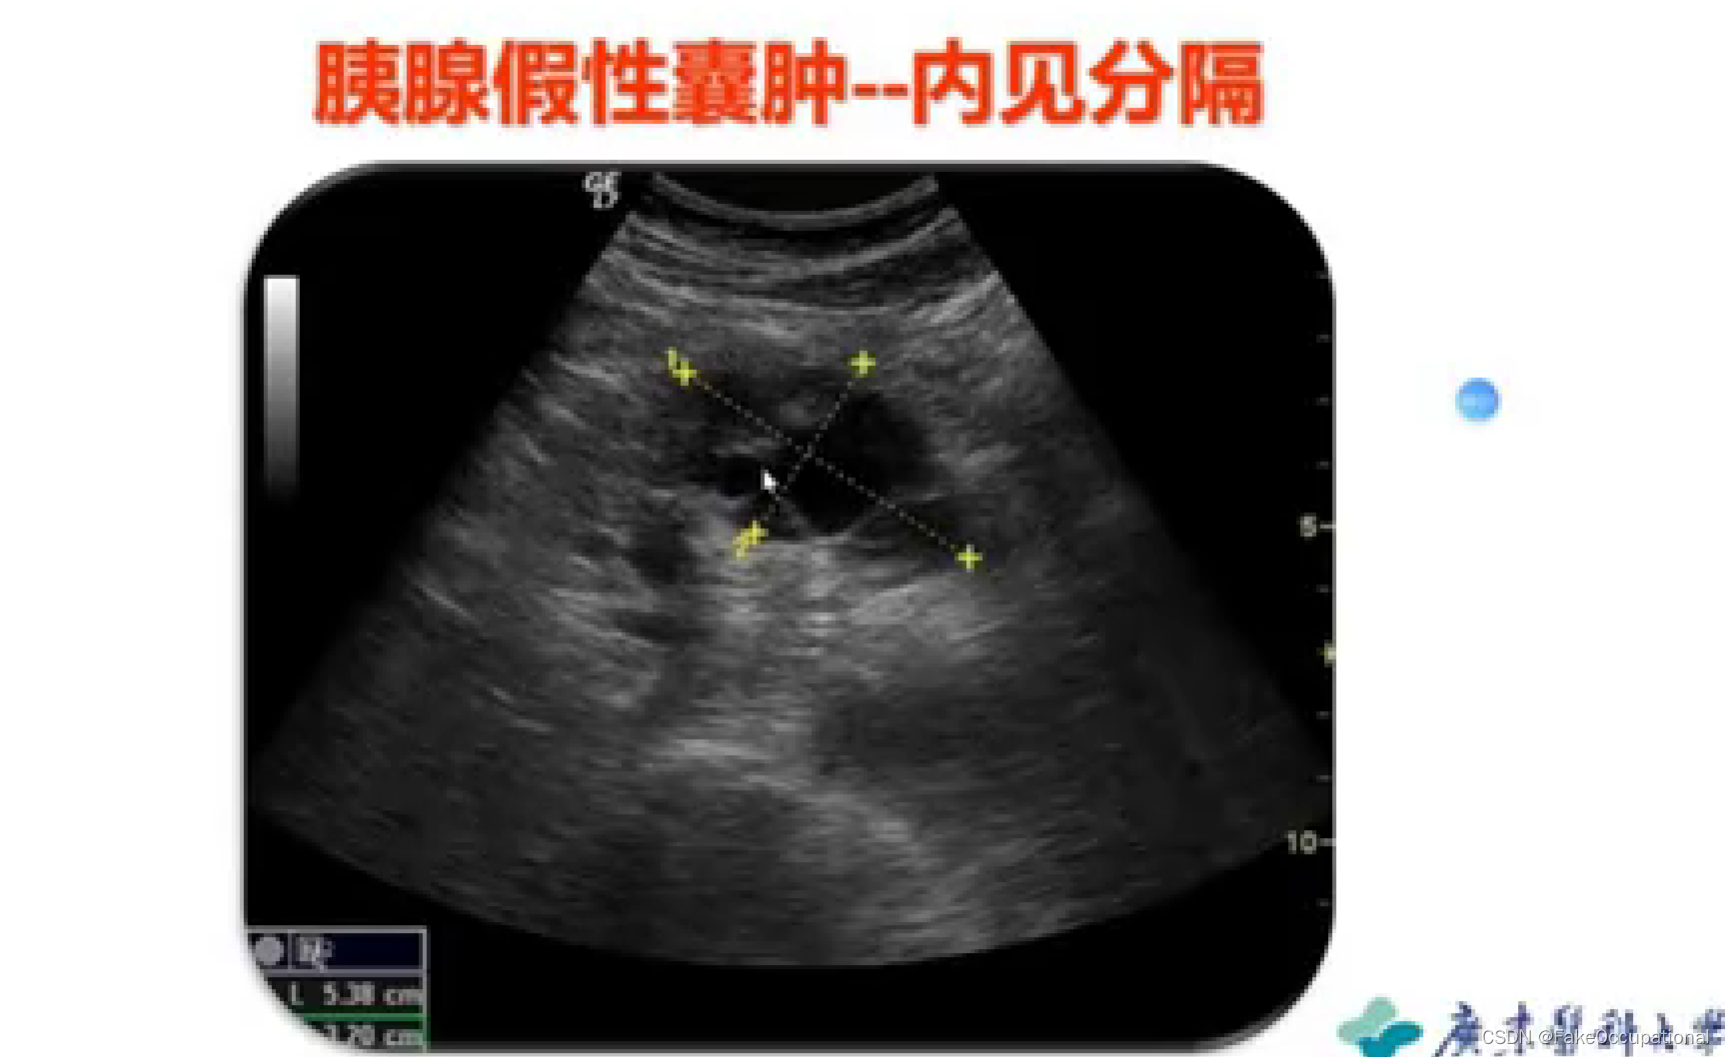

胰腺囊肿—假性囊肿、真性囊肿

胰腺真性囊肿

临床: 胰腺本身形成的囊肿,囊液由囊壁的上皮细胞分泌而来,多数没有临床症状,囊壁比较薄,内透声好.

分类:先天性囊肿

猪留性囊肿

寄生虫性囊肿